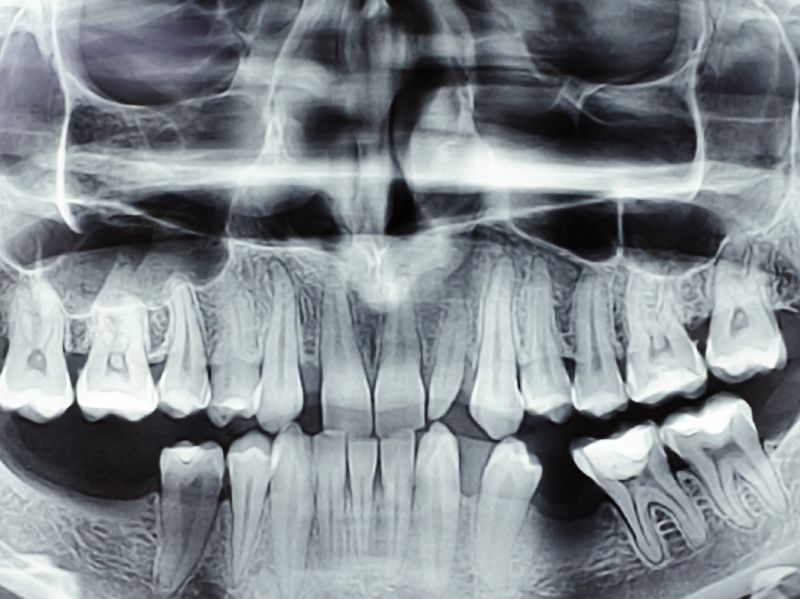

补的义齿以后还会有龋病吗

补了义齿之后,是有可能得龋病的,叫继发龋。一般补牙之后,医生会告知病人,补牙并不是一劳永逸的事情。补牙之后每年都要检查,因为充填体和本身的牙齿之间并不是完全密合,还是有微渗漏的,会导致边缘的继发龋。此外,牙齿有好几个面,咬合面、唇面、舌面,补了颌面可能下次邻面又发生发生蛀牙。 详情»

浅龋需要补吗

浅龋需要补牙。一般来说,如果浅龋处于牙齿表面,蛀洞较小且没有引起疼痛,可以通过改善口腔卫生习惯和定期洁牙来控制龋齿的发展,而不一定需要马上进行补牙。例如,可以加强刷牙和使用含氟牙膏,控制糖分摄入,少吃粘性食物等措施来帮助改善龋齿的情况。然而,如果浅龋已经扩大,牙釉质变软并且有蛀洞形成,就应该及时进行补牙了。因为如果不及时进行治疗,蛀洞会继续扩大,最终导致牙髓感染,引起剧烈疼痛和牙齿松动。此时,需要到正规的口腔诊所进行检查,由专业牙医判断是否需要进行补牙治疗 详情»